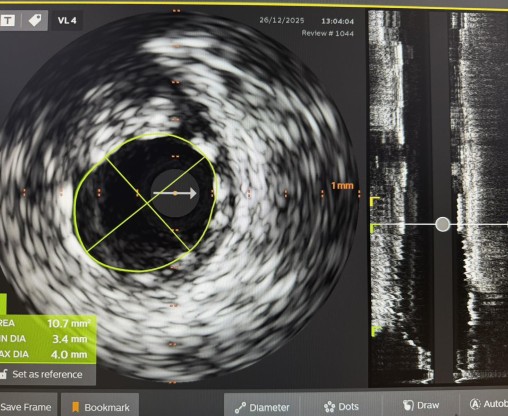

„Pacijent je imao simptome angine pectoris. Nakon urađene koronarografije verifikovana je teška trosudovna koronarna bolest, gdje su bolesne bile desna koronarna arterija, dok je na lijevoj strani kritično mjesto bilo na glavnom stablu  odakle ide račvanje u dvije grane. Takvi pacijenti uglavnom završavaju na kardiohirurškom konzilijumu i na operaciji bajpasevima. Međutim, odluka konzilijuma u Banjaluci je bila da se, zbog godina života pacijenta,  radi perkutana intervencija na desnoj i lijevoj koronarnoj arteriji uključujući glavno stablo.Takve procedure zahtijevaju da se rade sa kontrolom imidžinga, savremene intravaskularne dijagnostike (IVUS), što smo mi i uradili. To dodatno povećava bezbijednost i preciznost zahvata. Procedura je trajala svega 45 minuta, a pacijent je već narednog dana otpušten kući“, izjavio je dr Janjičić.